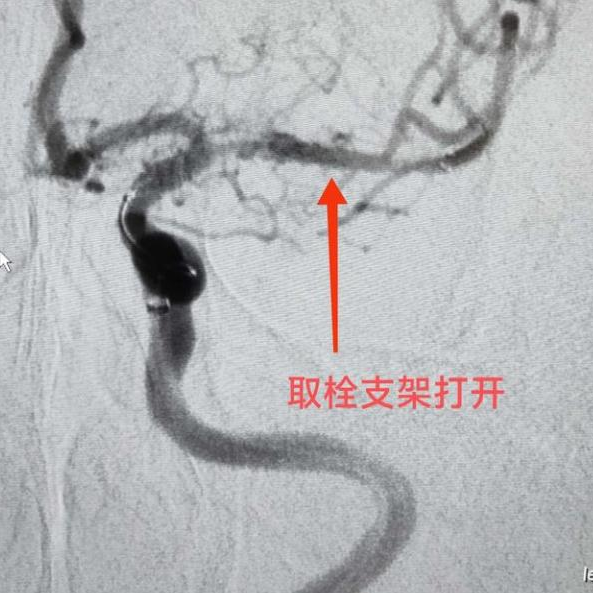

??打开取栓支架,血管再通